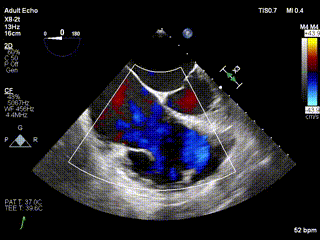

三例患者入院后,葛均波院士團隊周達新教授、潘文志教授、張源博士、陳莎莎博士及心超室的潘翠珍教授、李偉教授對患者的情況進行詳細評估和討論,最終決定為三例患者選擇LuX-Valve Plus40mm、50mm和50mm型號的瓣膜進行手術治療。手術后即刻拔除氣管插管,術后患者三尖瓣反流癥狀得到顯著改善,復查心超結果顯示人工三尖瓣瓣膜支架固定穩定,瓣葉關閉形態未見異常,未見明顯反流。